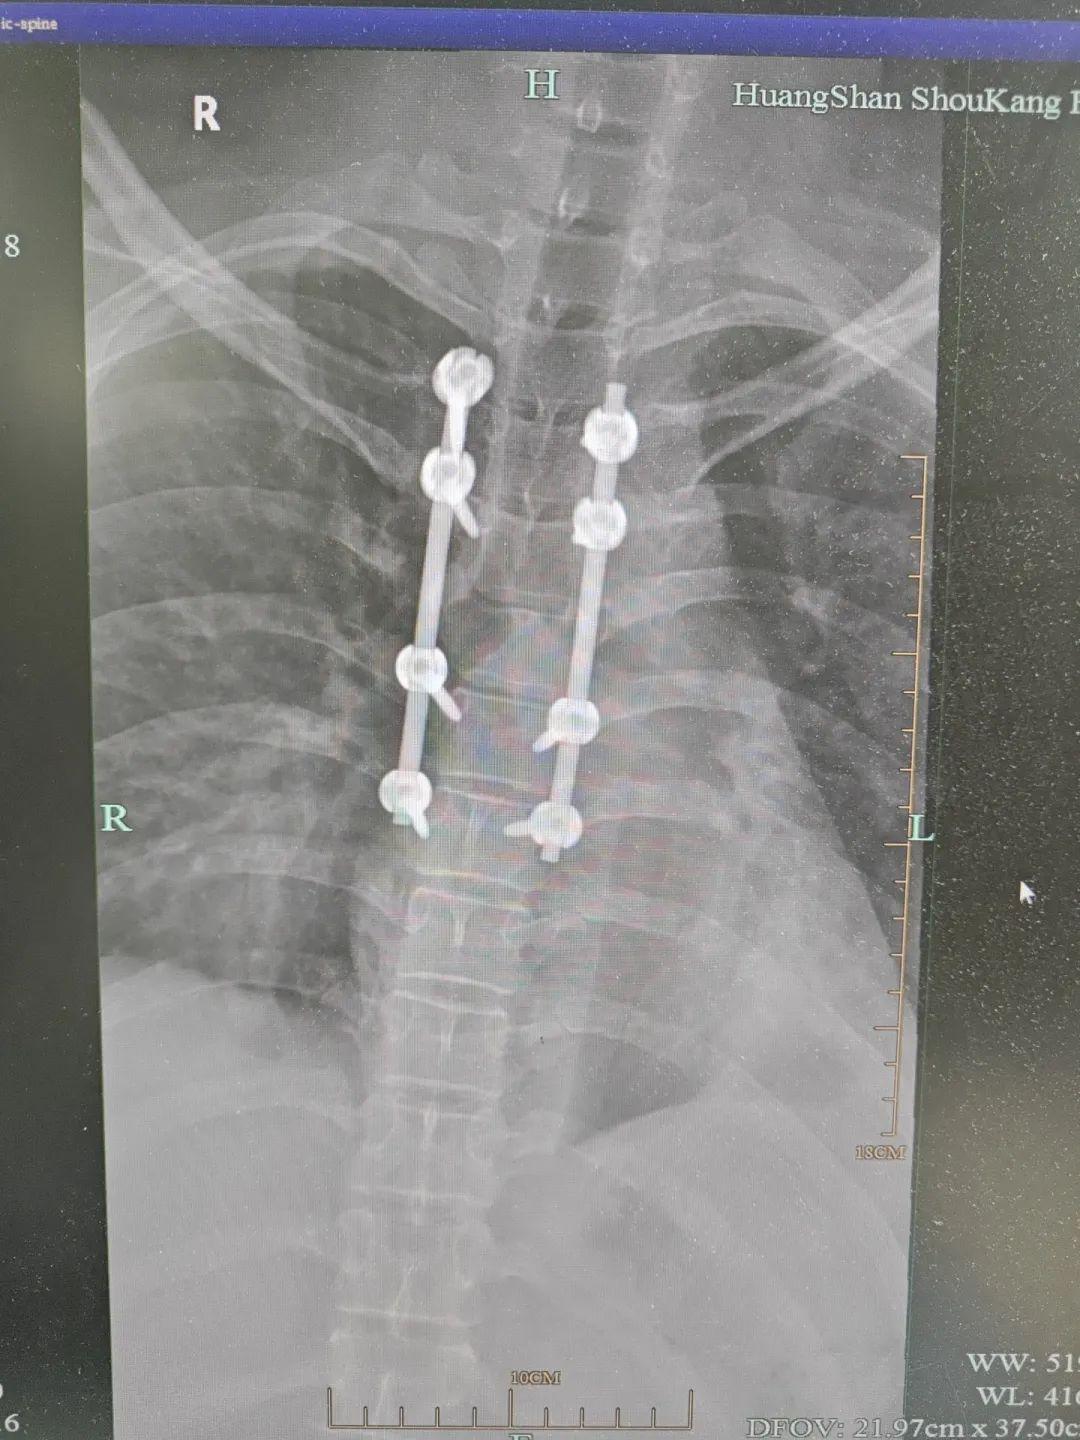

几日后,方大标主任带领团队实施了决定毕某命运的一场手术——胸5、6椎体占位伴椎管狭窄后路椎管减压+钉棒内固定术+病理活检术。医生们分块切除了压迫脊髓的肿瘤瘤体,成功完成了椎管减压。

▲术后摄片示内固定在位,脊柱稳定性得到重建